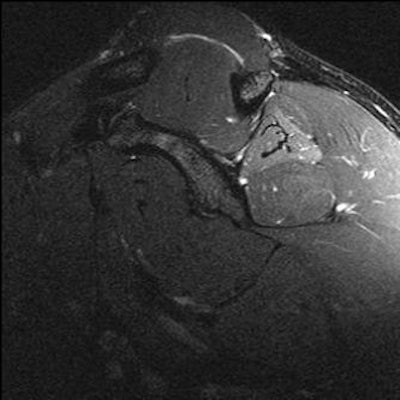

| Images from a prior Combine event. Player with right shoulder pain. Oblique sagittal fat-saturated T2 MR images of the right and left shoulders. Increased signal in the right infraspinatus muscle suggests denervation edema, possibly caused by mass effect from markedly hypertrophied supraspinatus muscle causing pressure on the adjacent suprascapular nerve. |

![]() |